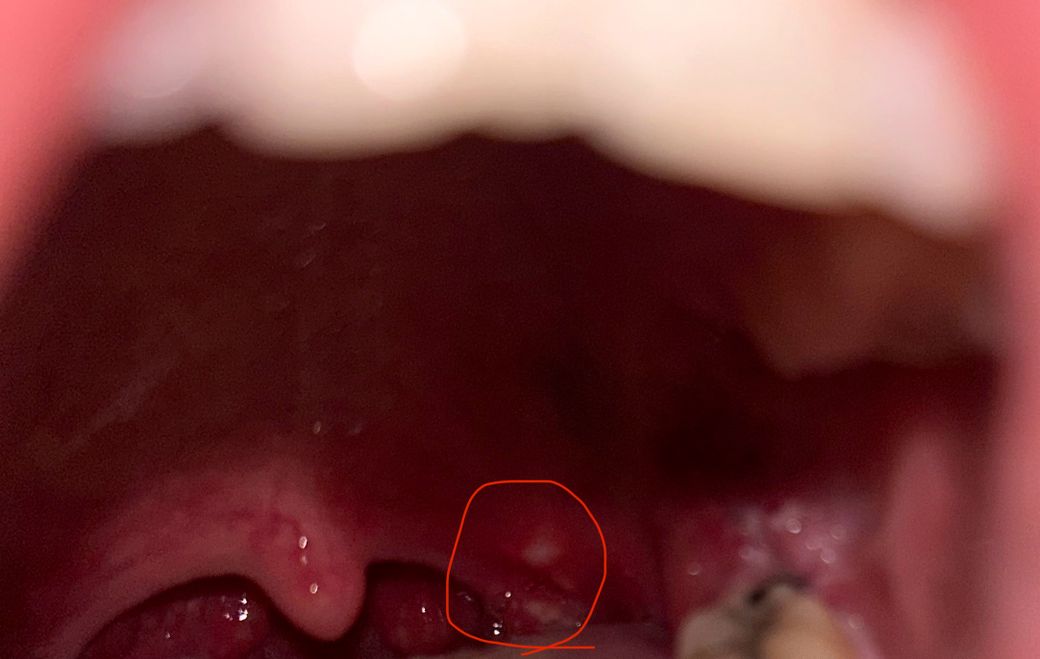

사랑니 발치 후 3일차인데 어제 저녘부터 목이 너무 아파서 목이 부은겅가 생각했는데 보니까 이런게 생걌어요 보면서 확인해보니까 이거때문에 아픈게 맞는거같은데

이거 구내염인가요?